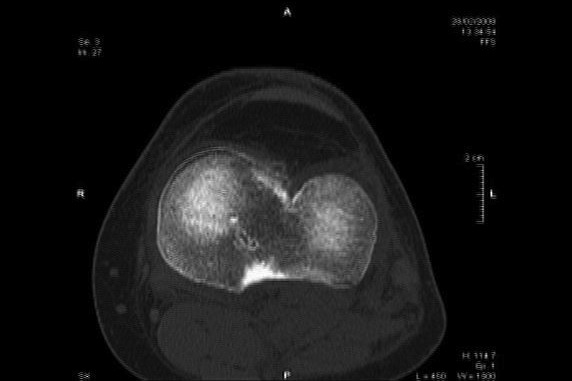

A type of knee injury that's familiar to many athletes may not always require surgery right away. Hi, I'm Dr. Cindy Haines, host of HealthDay TV. Injuries to the anterior cruciate ligament in the knee - also known as the ACL - are most common in young people who are physically active. These injuries can lead people to become less active and have trouble using their knee. ACL tears are commonly repaired with surgery, and more than 200,000 ACL reconstructions are done each year. A new study in the New England Journal of Medicine followed 121 young, active adults with ACL injuries. Some of them began rehabilitation for their knee and also had surgical reconstruction of the ligament soon after the injury. The rest had rehab, but put off surgery until later if necessary. After two years, both groups had similar improvements in pain, symptoms, ability to perform sports and recreational activities, and knee-related quality of life. By reserving the surgery as a later option, more than half of ACL reconstructions might be avoided without compromising results, according to the researchers. But as another expert pointed out in the journal, these injuries should be handled on a case-by-case basis. IÕm Dr. Cindy Haines of HealthDay TV, with the news that doctors are reading; health news that matters to you.